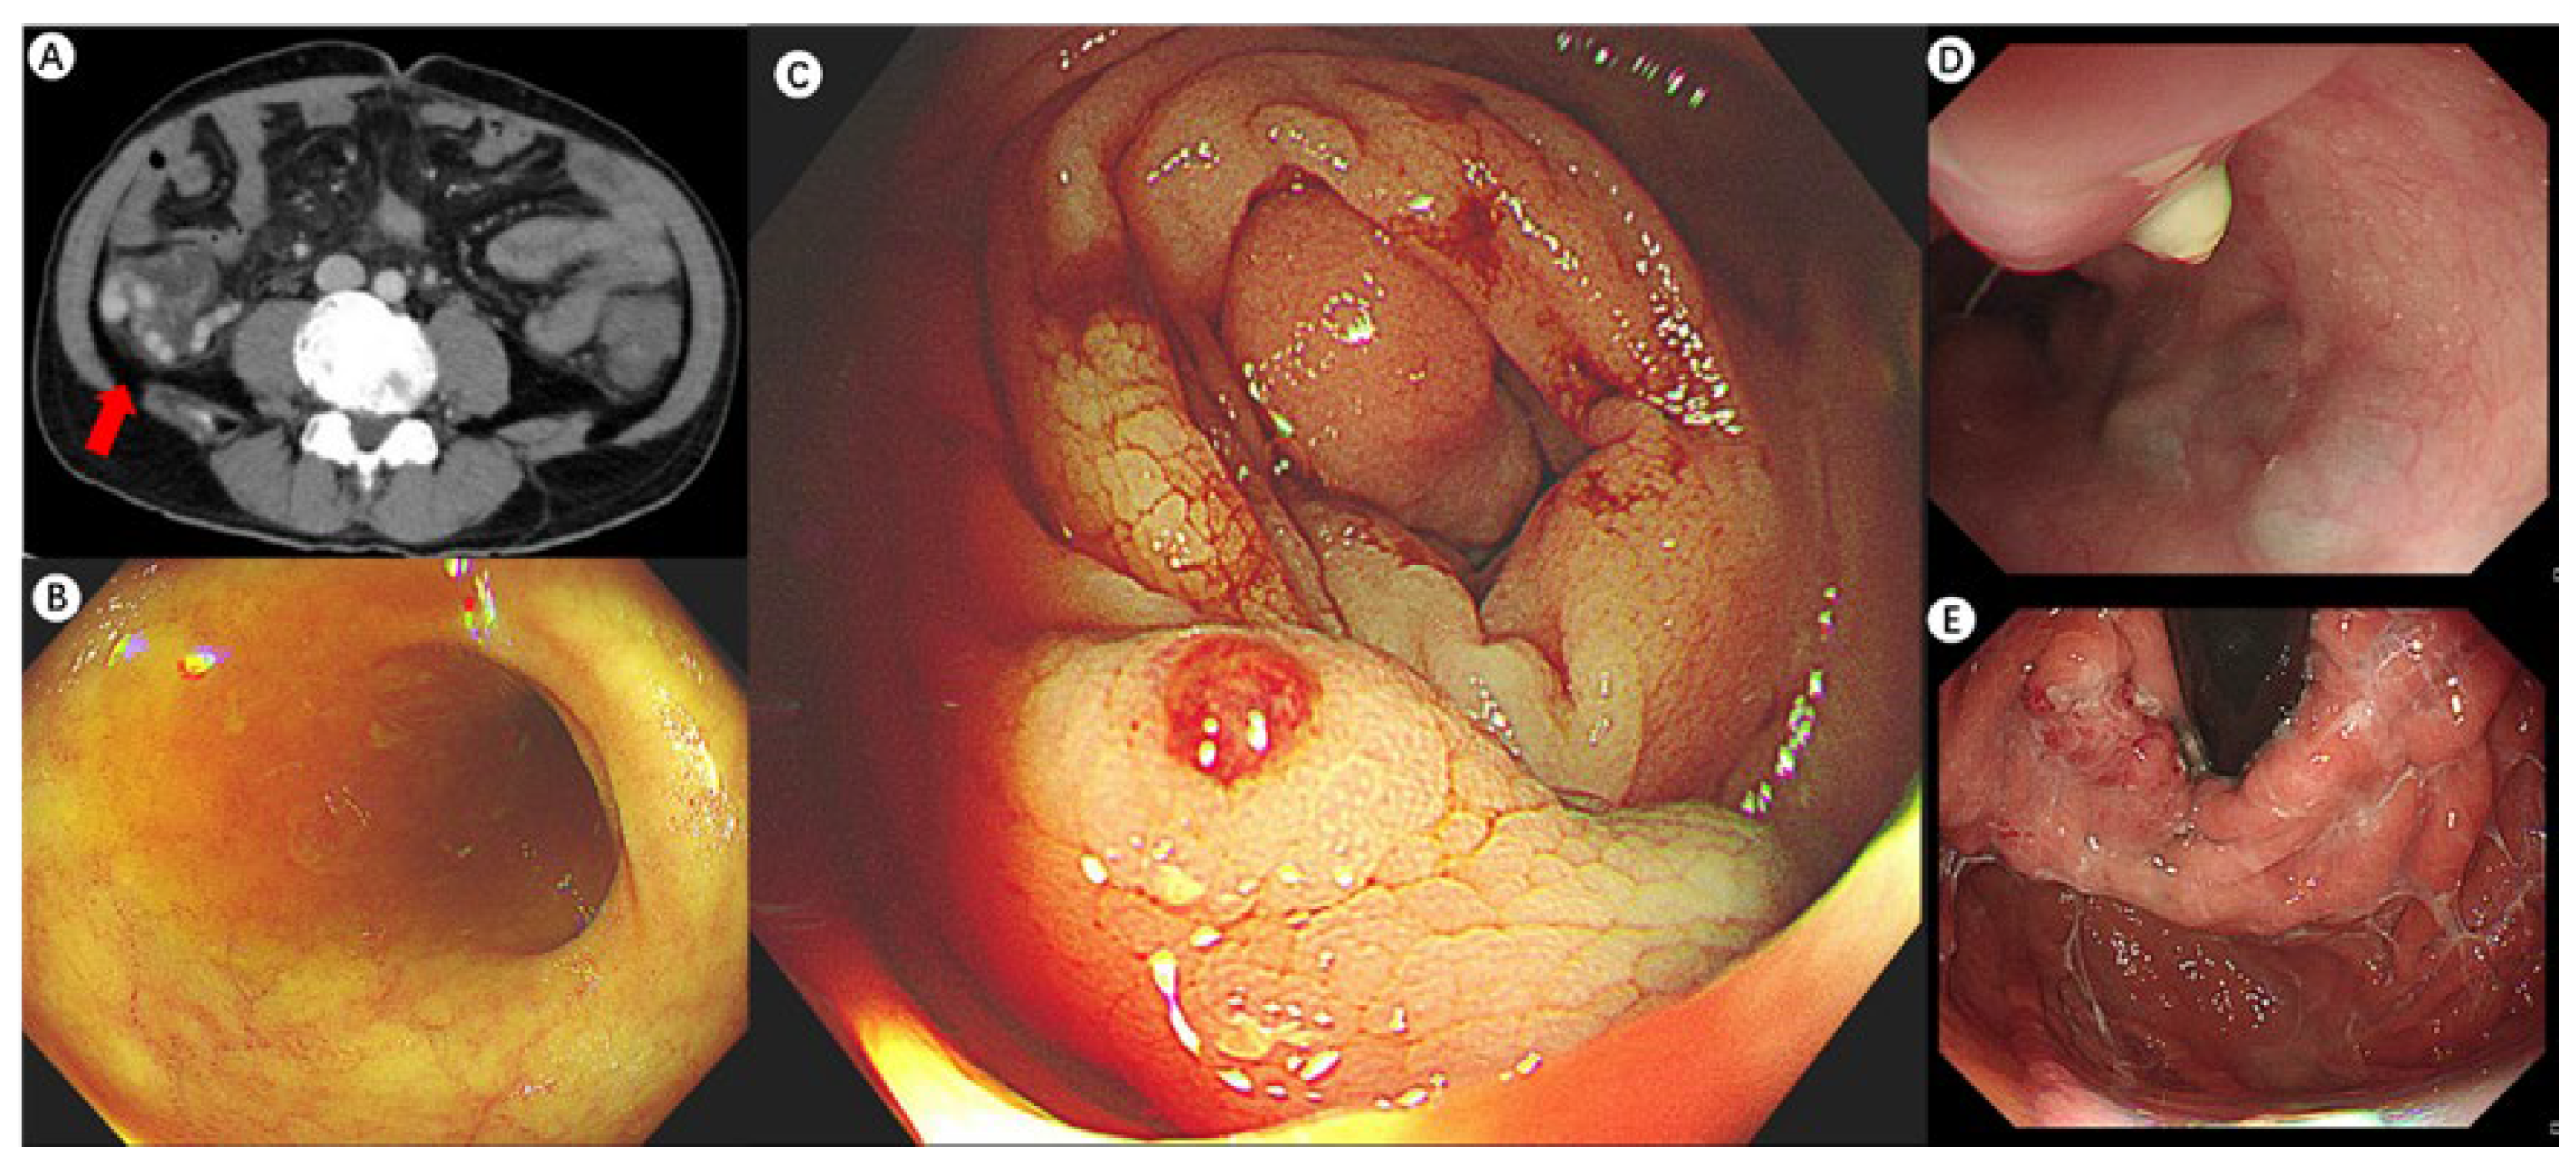

A 46-year-old man with hepatitis C-associated cirrhosis presented with severe fatigue and a one-month history of dark red bloody stools. A previous gastroscopy at a local hospital revealed moderate gastric–oesophageal varices without active bleeding. Endoscopic sclerotherapy and cyanoacrylate injection were performed as preventive measures. However, ongoing bleeding and a decline in the patient’s overall condition required his transfer to our hospital. Upon admission, his vital signs were at the lower limit of normal, and clinical examination showed anemia, mild jaundice, and active bowel sounds. Blood tests indicated low hemoglobin levels with normal urea nitrogen, and his Child–Pugh score was 11, consistent with advanced liver dysfunction. Based on the presence of dark red stools and normal urea nitrogen levels, the findings indicated lower gastrointestinal bleeding. Enhanced CT scan indicated tortuous thickening of blood vessels in the right abdominal cavity (the red arrow), raising suspicion of ectopic varices (A). An urgent colonoscopy provided additional clarity, revealing a clear view of the terminal ileum (B) and a submucosal protrusion with a thrombotic head in the ascending colon (C), confirming this as the site of the recent bleeding. A repeated gastroscopy showed evidence of prior therapeutic interventions for GOVs, which were stable (D,E). Notably, the patient had a prior episode of esophagogastric variceal bleeding one year earlier, which was successfully treated with ligation and cyanoacrylate injection. Evidence suggests that in the management of varices in portal hypertensive patients, precise identification of the bleeding target and minimizing unnecessary treatments may lead to more benefits for patients. Revealed risk factors of ectopic varices include portal hypertensive gastropathy, a history of abdominal and pelvic surgeries, and in this case, advanced Child–Pugh score and endoscopically eradicated esophageal varices. There is evidence suggesting that the impulsive occlusion of varices that is not responsible for active bleeding may increase the risk of hemorrhage from other sites. A study involving patients with PHT ectopic varices (n = 73) revealed that 57.9% of patients with ectopic varices had a history of treatment for esophageal varices, with an average interval of 2.8 ± 1.3 years in the rectum and 2.3 ± 2.1 years in the duodenum [1].